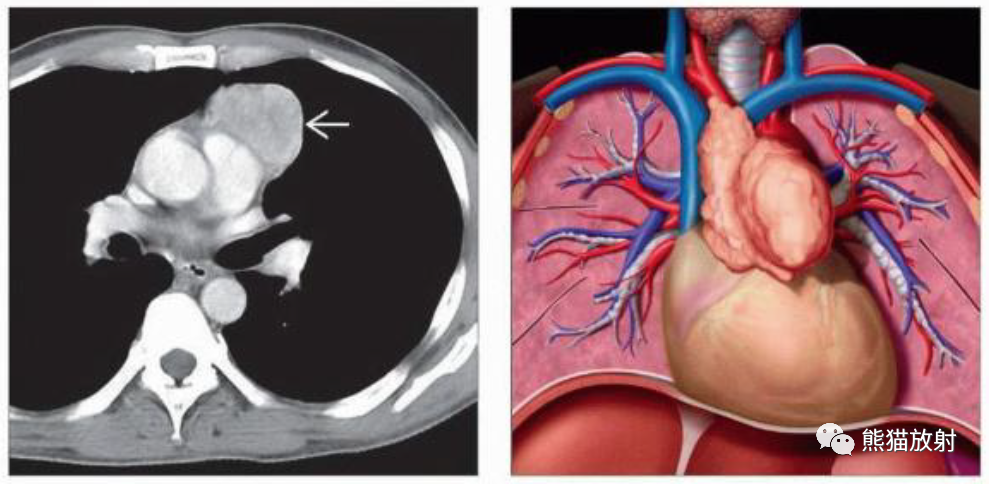

(左) 胸腺瘤患者的CT显示前纵隔肿块,表现为不均质强化,病变位于左前纵隔,紧靠邻近的肺动脉干,未见明显的血管侵犯。胸部CT上缺乏组织分界并不能可靠地提示局部浸润。

(右) 胸腺瘤的形态学特征,胸腺瘤是一种原发性肿瘤,典型表现为肿瘤起源于胸腺的1个叶,通常表现为单侧生长。